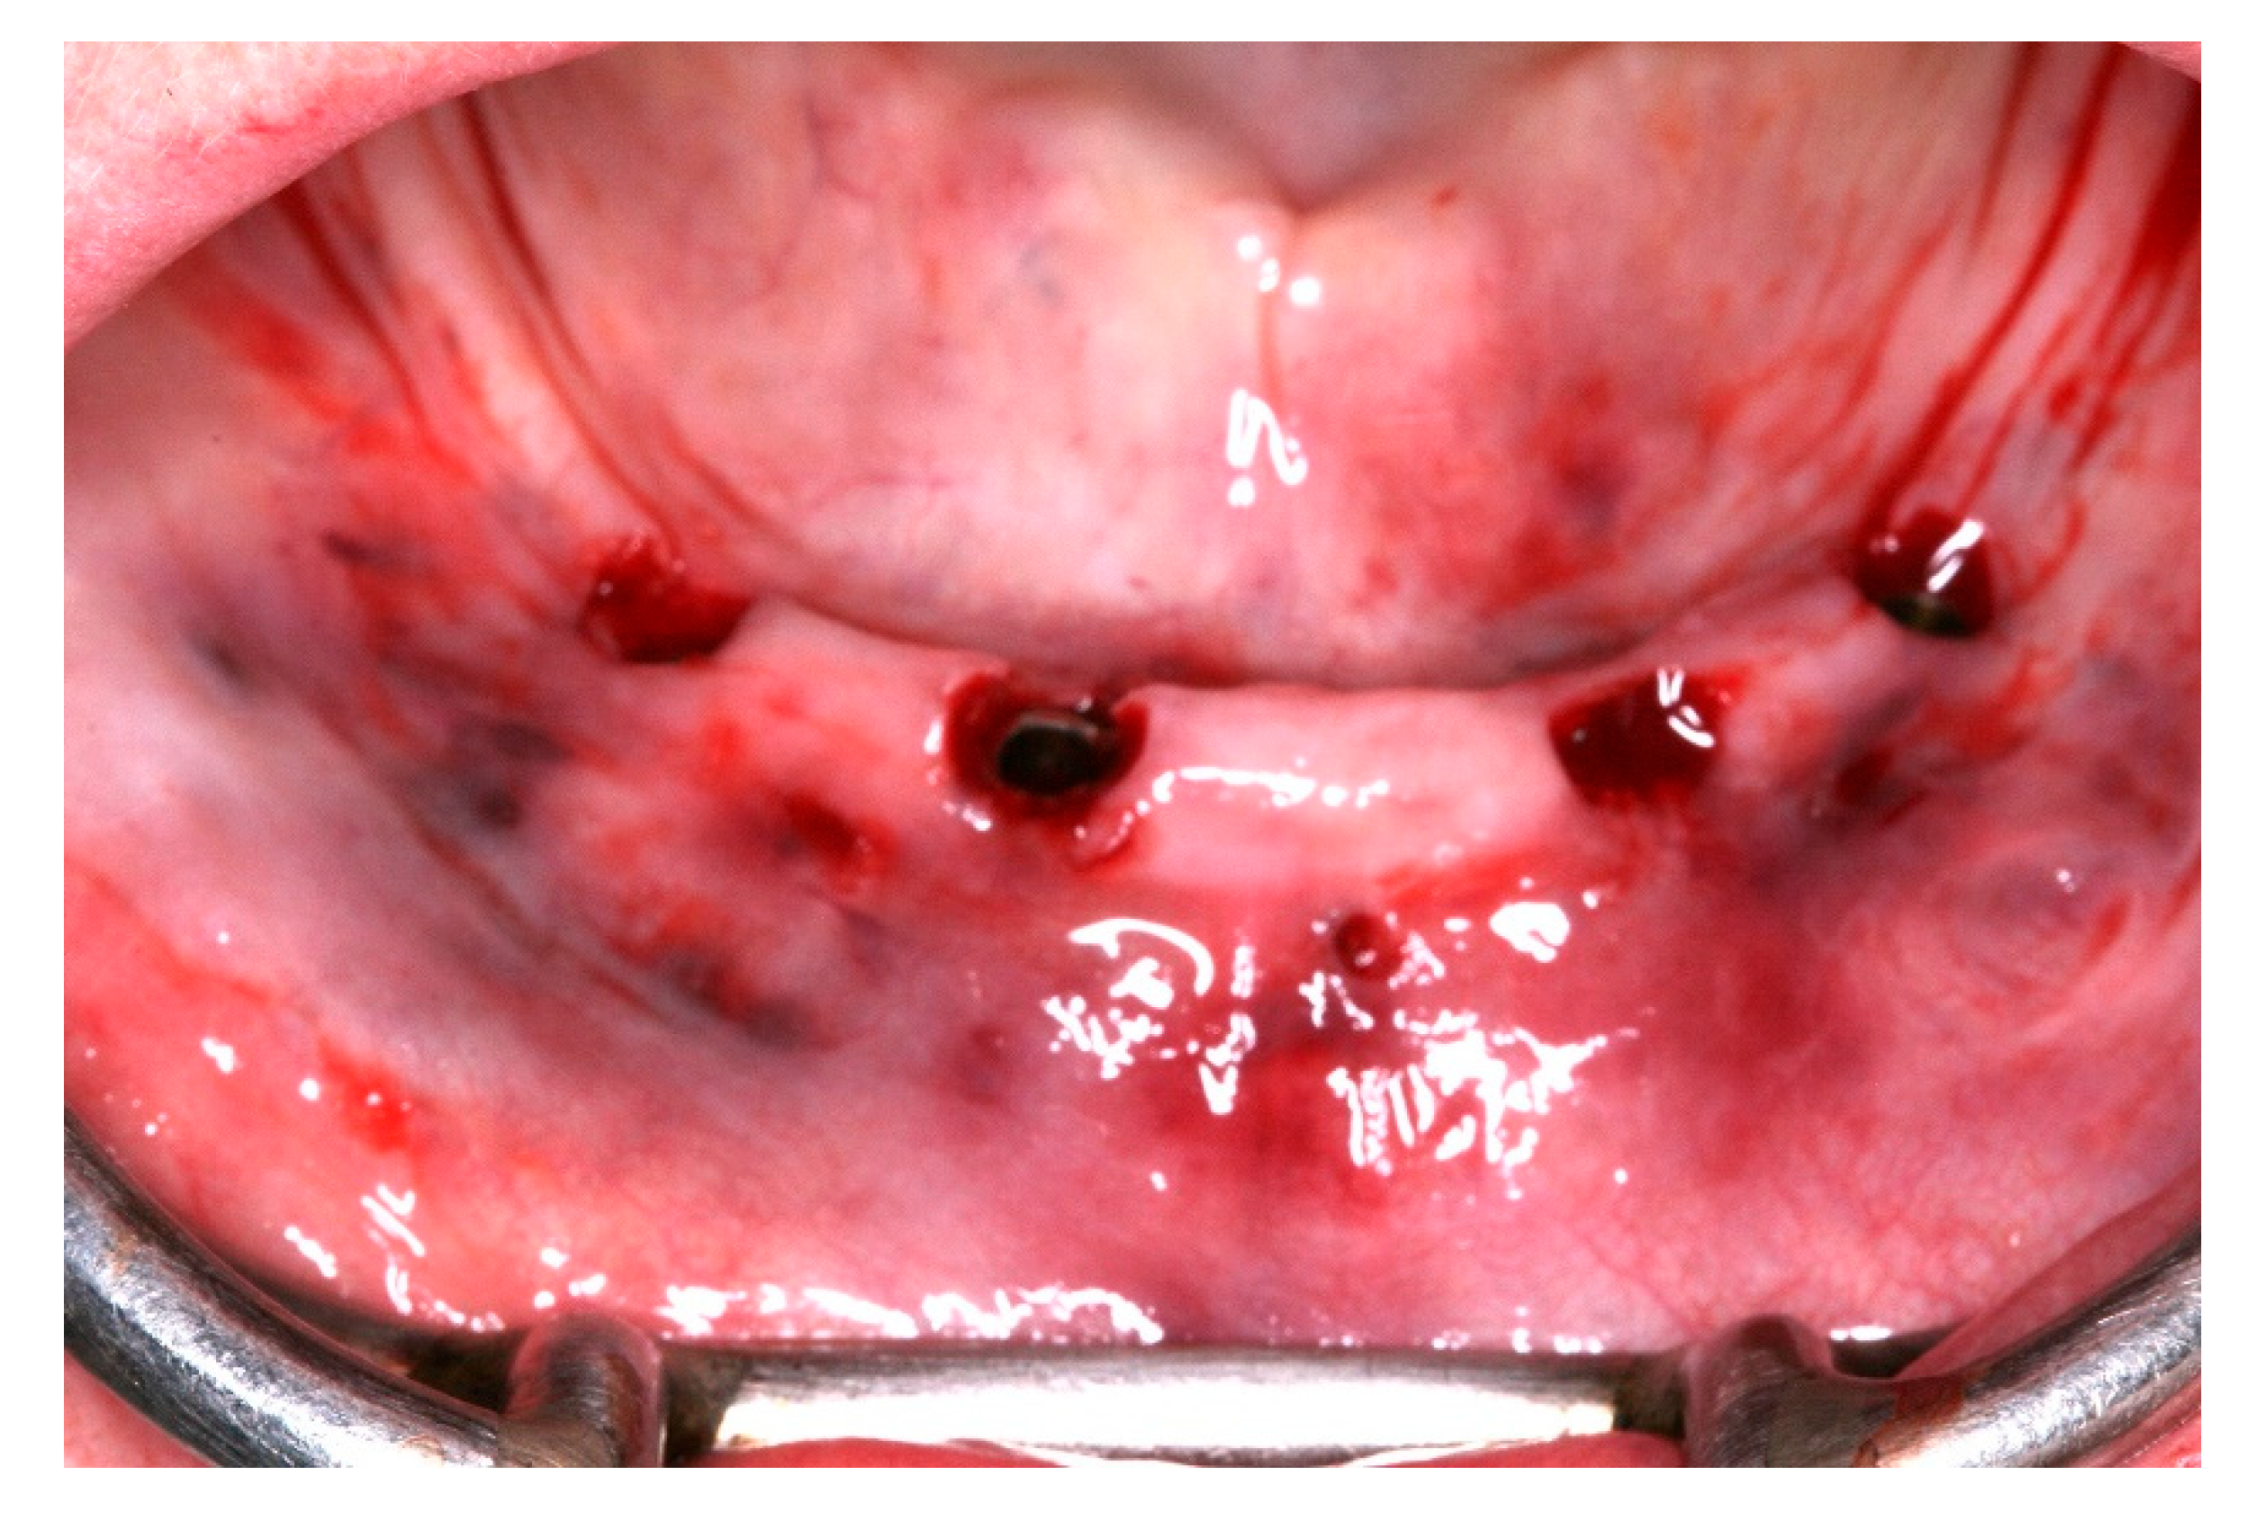

Figure 1. Initial view of the patient’s lower mucosa.

Figure 11. View of the mucosa immediately after surgical guide removal and implants placement.

After a healing period of 3 months the patient returned to change que temporary fixed prothesis for a new one, more delicate and with a reinforced metallic bar for a better ferulization of the implants and better dissipation of the stress during function. After removal of the temporary prosthesis we could see the peri-implant mucosa was healthy (Figure 19), without bleeding on probe nor peri-implant sulcus with more than 3mm depth, even around the implants were there were lack of a satisfactory keratinized tissue band, showing us that the patient was being able to maintain the cleansing of the region below the prosthesis. A new fixed rehabilitation over the implants was produced (Figure 20, Figure 21 and Figure 22). 2 years after the surgery we could see on a control panoramic radiograph no signs of bone remodeling above the expected around the implants (Figure 23).